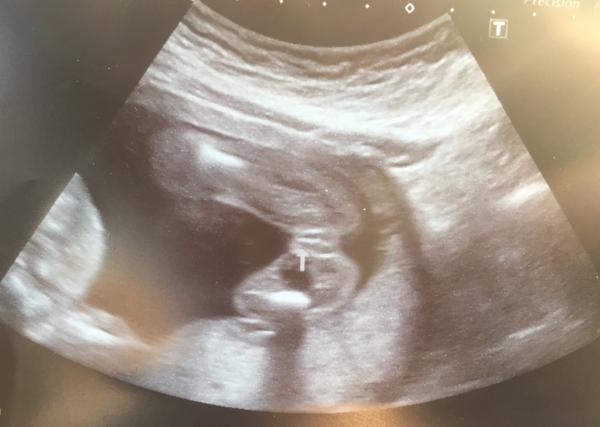

Je to holka, nebo kluk? 🙂 Co myslíte?

Zdravím holky, poradíte???? je to kluk, nebo holka???pan doktor se přiklání k holčině, já vidím pindíka🙂))

z tohodle řezu to fakt nejde zjistit🙂 to co je tam označené může býtk klidně nějaká z končetin, takže věřit doktorovi

já tam nevidím nic (pardon) chtělo by to kvalitnější ultrazvuk anebo věřit doktorovi 🙂

Neni to koncetina🙂) je to opravdu prirozeni. Potvrzeno lekarem. Ted jen odhalit jake🙂))

je to špatně vidět, chtělo by to lepší ultrazvuk. 🙂

no, mě osobně to přijde jako kávové zrno a to by ukazovalo na holčičku, ale pokud se dr. přiklání k holčičce, asi bych věřila... koukám, že jste 18tt, to je ještě docela brzy na přesné určení